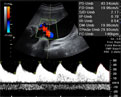

Ecografía Embarazo 2D y 3D - TERCER TRIMESTRE: Peso y tamaño del feto